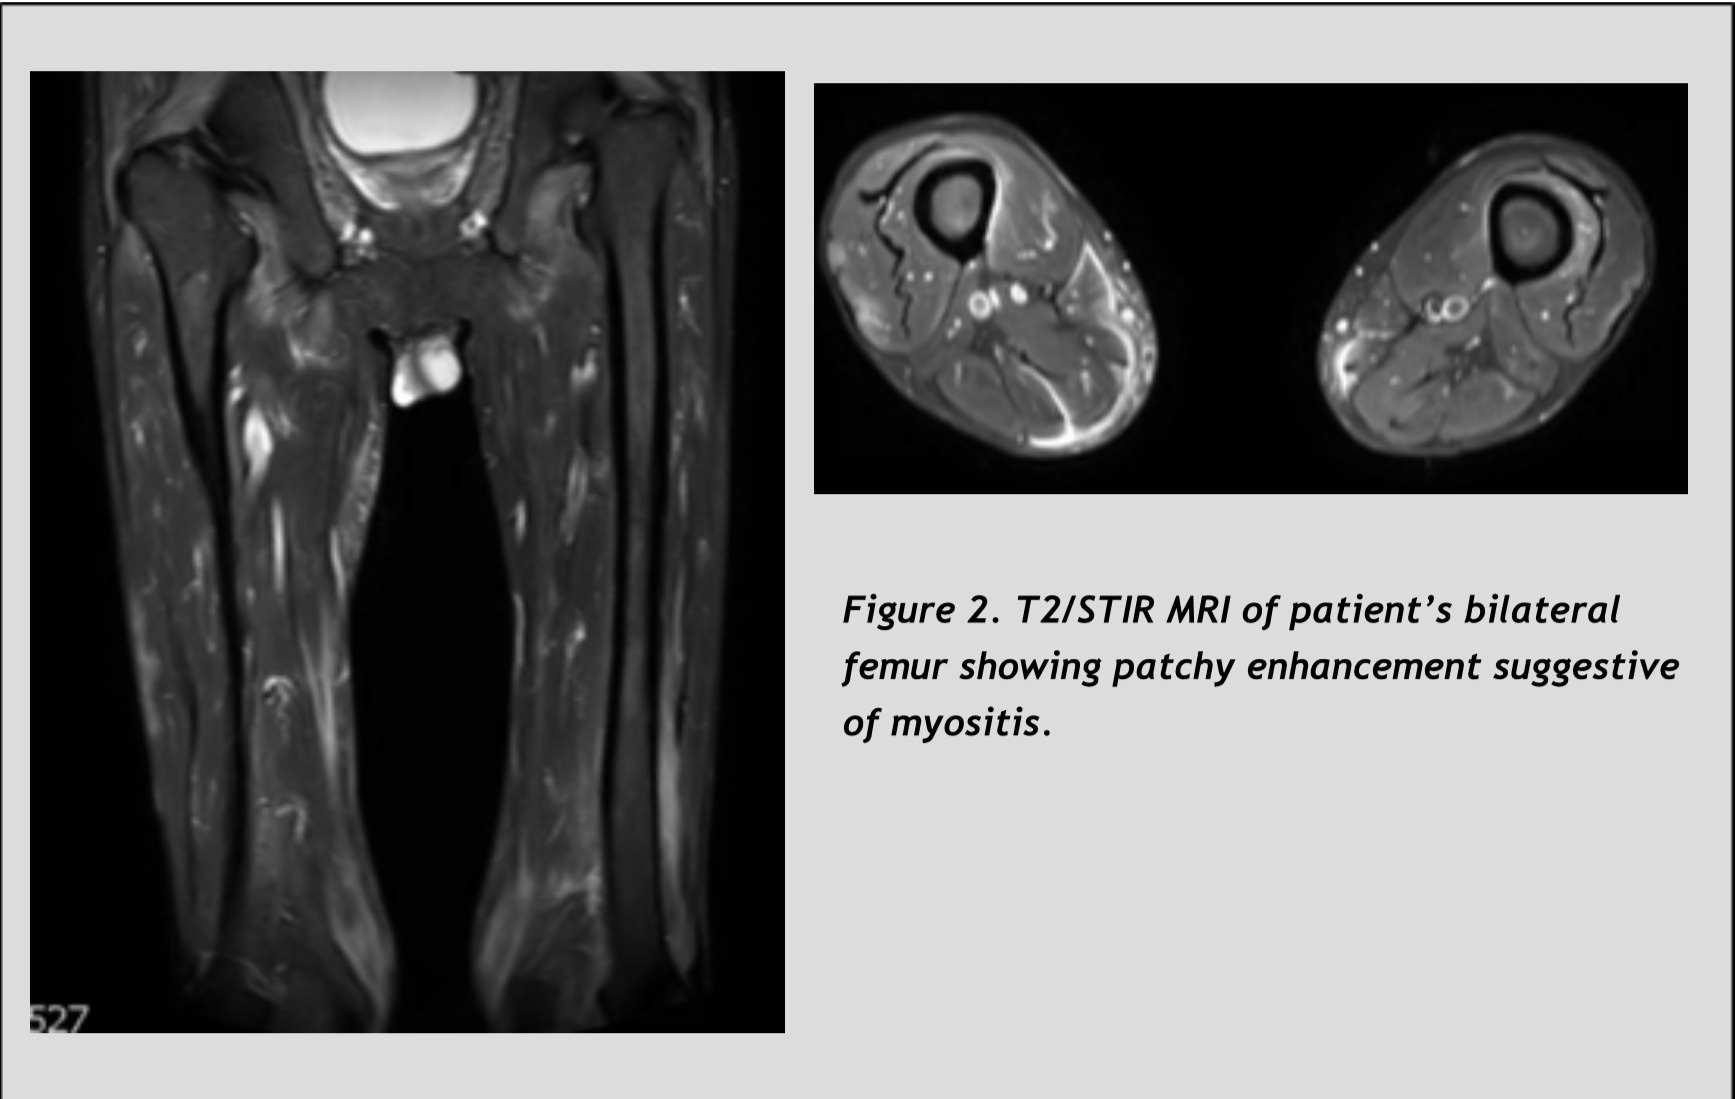

Case Presentation: 49-year-old man with history of alcohol abuse presented with a 3-month history of progressive weakness, weight loss and skin lesions. An outside dermatologist had diagnosed the patient with porphyria cutanea tarda (PTC) one month prior to admission based on characteristic skin findings on physical examination, and elevated urine and serum porphyrin levels. He presented to an outside hospital with failure to thrive, progressive weakness and weight loss despite one month of treatment with Plaquenil. Despite extensive evaluation, no unifying diagnosis was found for the cause of his symptoms. Vitals were stable on transfer. Physical examination was notable for cachexia, erythematous lesions over the MCP joints, and hyperpigmentation of his face, neck, and back. There was proximal weakness of his upper and lower extremities on neurologic exam. His labs were notable for an elevated ESR and CRP, with mildly elevated AST and ALT (with AST > ALT). His CK was normal, comparable to the level tested one month prior. Serum aldolase was elevated. Rheumatology and Dermatology were consulted to evaluate for dermatomyositis. The patient underwent upper extremity skin biopsy, with findings that were consistent with dermatomyositis. MRI of his thighs revealed myositis and muscle biopsy showed tissue necrosis, which confirmed the diagnosis. CT chest/abdomen/pelvis did not show signs of malignancy. Treatment with prednisone was initiated.